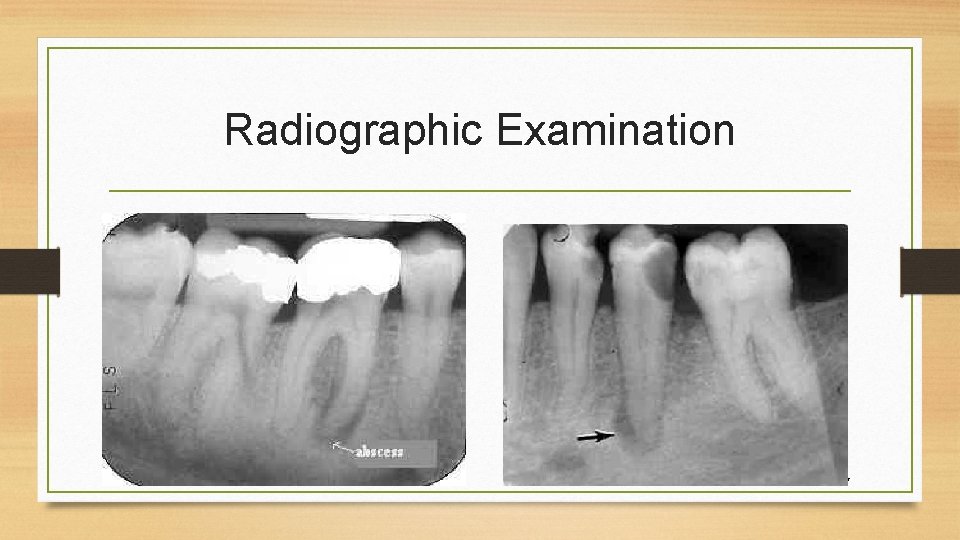

Radiographic Examination 7